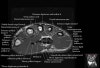

- Axial section

Axial T1 evaluates the tendons of the wrist and carpal tunnel, including the flexor retinaculum.

Axial PD fat suppressed evaluates the tendons of the wrist and carpal tunnel, including the median nerve.